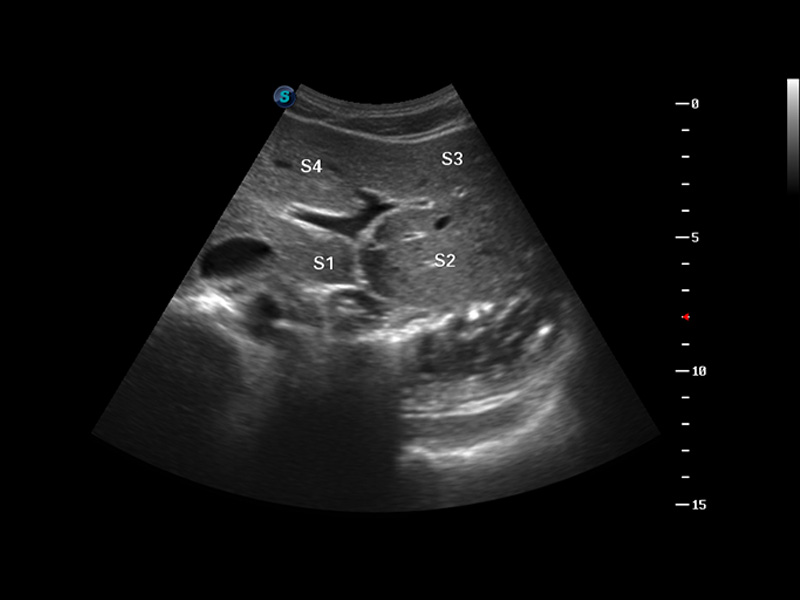

S8 EXP便携式彩色多普勒超声诊断仪是1xBET研发的高端全身应用型便携彩超。高通道的VIS平台融合可视化(Visual)、智能化(Intelligent)和人性化(Smart)的特点,配以1xBET自主研发生产的探头大家族,使您能够快速、准确的获得病人信息,提高工作效率的同时减轻疲劳。

成像技术

多波束形成器

μ-Scan微米成像

谐波成像

实时宽景成像

空间复合成像

3D/4D成像